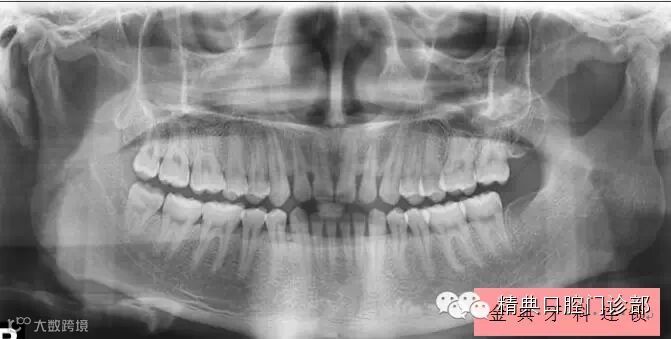

图片九、此时您需要到来洗牙,填写好资料信息后,首先会给您拍一张牙齿X光片(全景片),医生通过全景片为您的牙齿做个全面诊断(张嘴观看会看不到问题,比如牙根),您很有必要了解自己每颗牙的健康状况。